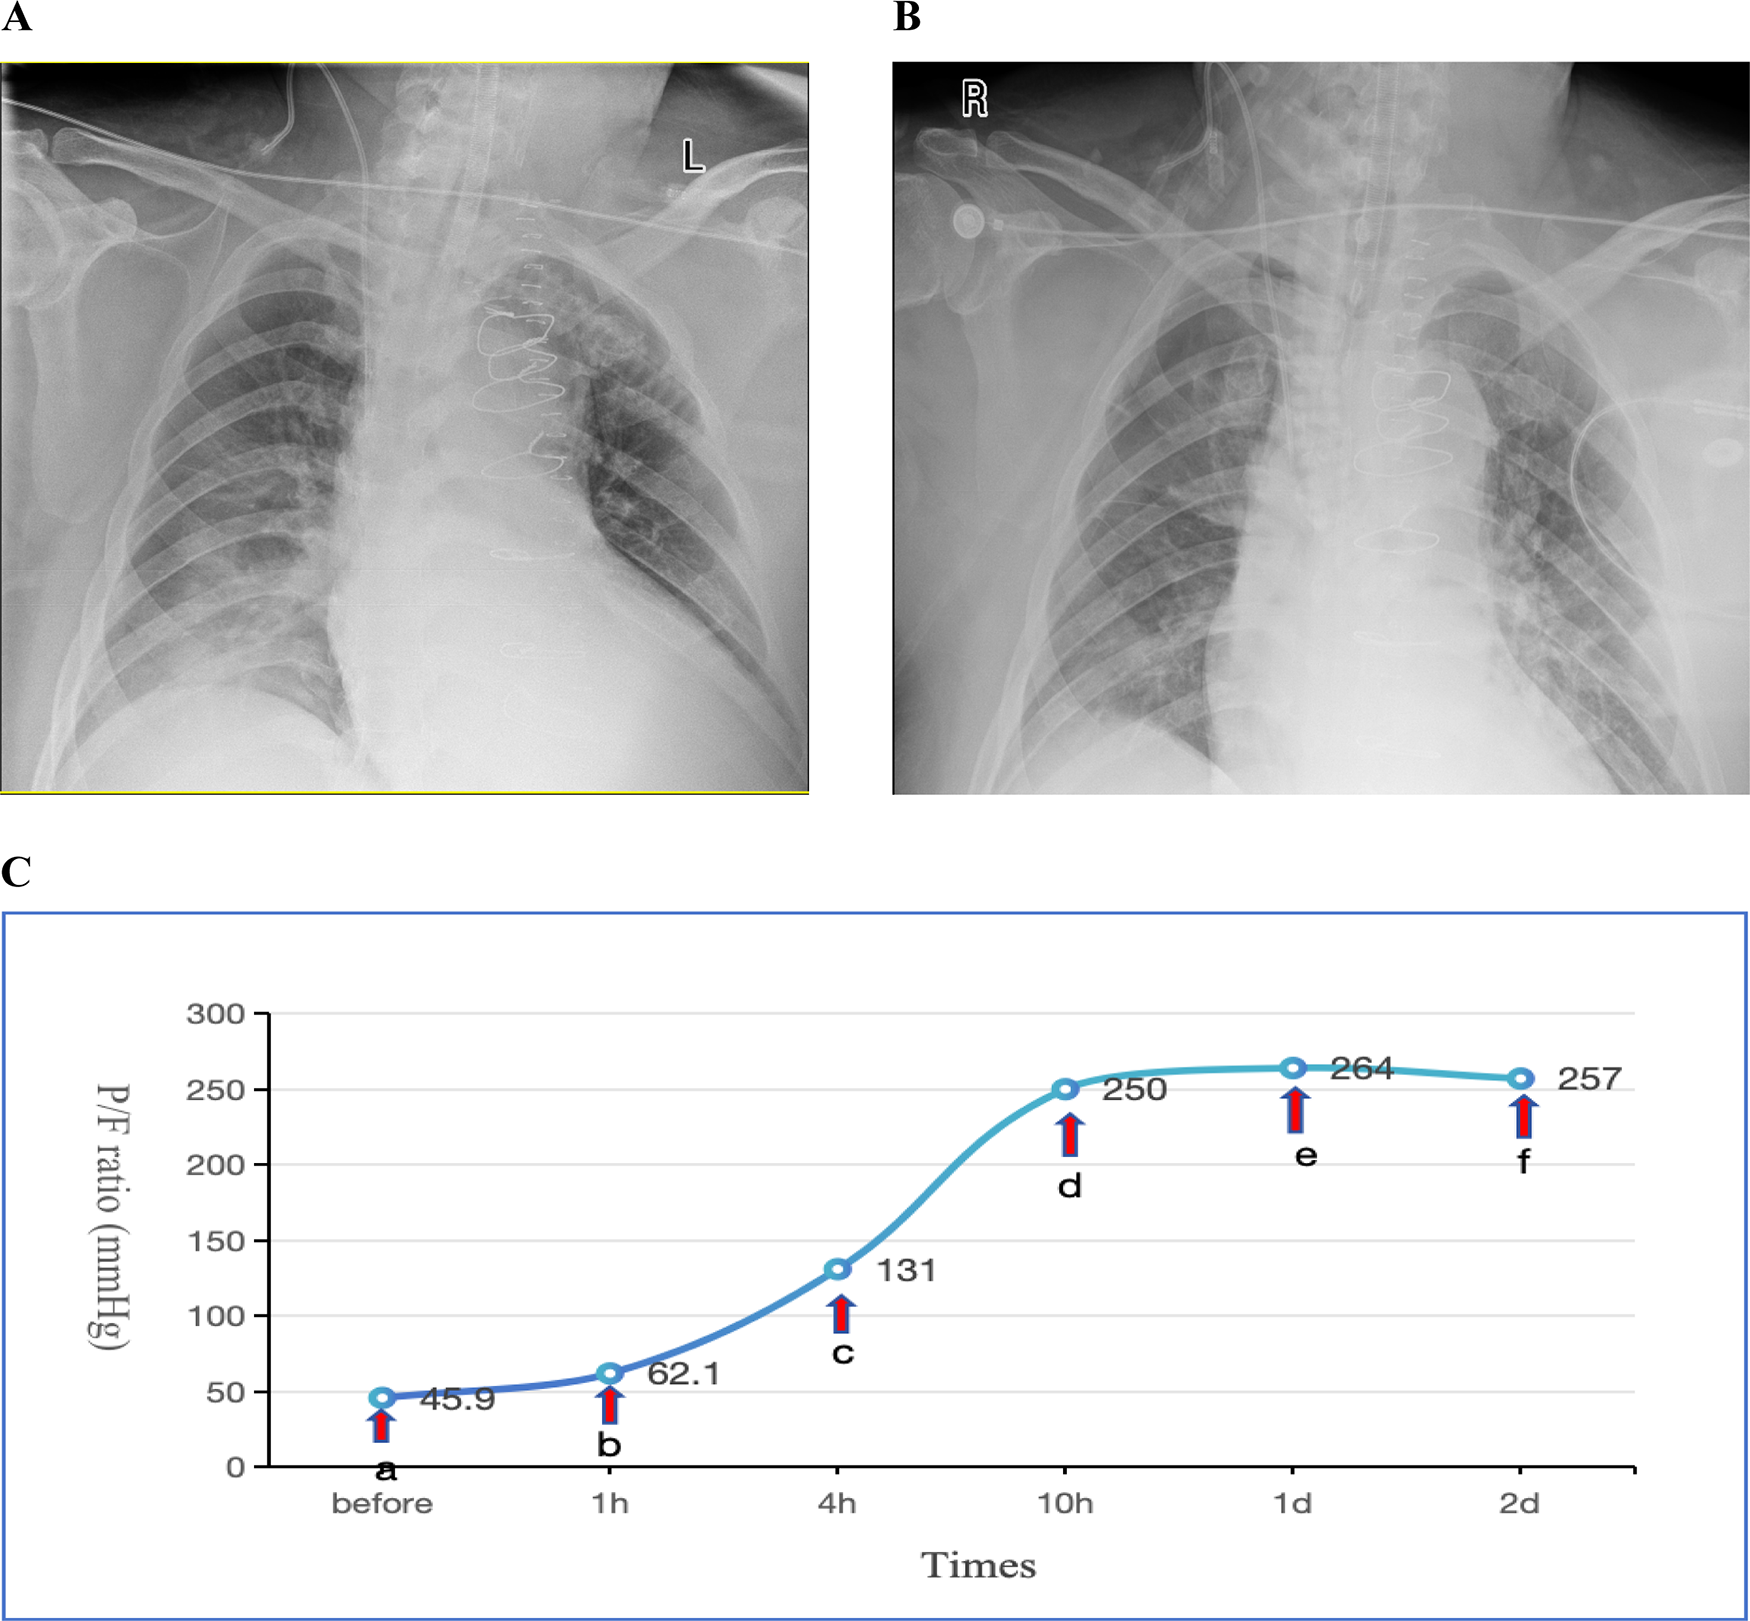

(PEEP) set between 10 and 15 cmH2O. Methylprednisolone 40 mg IV push twice daily (bid). For infection prophylaxis, clindamycin 0.6 g bid was administered during the first two postoperative days. By the second postoperative day, the OI still showed no improvement, and there remained no obvious signs of infection. Sputum production was not significantly increased, and inflammatory markers showed no notable upward trend. Drainage output had significantly decreased compared to the first postoperative day. INO therapy was initiated at a dose of 10 ppm based on Methylprednisolone 40 mg IV push twice daily (bid), leading to a marked improvement in oxygenation as evidenced by an increase in SpO2 from 88% to 98% within 30 min of administration. However, on the third postoperative day, the patient's OI deteriorated sharply, reaching a critical low of 45.9 mmHg. Vital signs showed a body temperature of 37.2°C. Endotracheal suction yielded minimal secretions. Physical examination revealed coarse breath sounds bilaterally, with diminished sounds on the right side. Bedside chest x-ray demonstrated bilateral minimal pleural effusions, right lung infiltrates, and partial resolution of right-sided effusion (Figure 1A). Echocardiography showed an LVEF of 60%, ruling out cardiogenic pulmonary edema. Inflammatory markers showed: WBC: 9.1 × 109/L, Neutrophils:85.1%, IL-6:17.3 pg/ml, CRP:174.3 mg/L (all showing downward trends from previous measurements). Given these findings, the patient was diagnosed with severe ARDS according the Berlin criteria. Immediate prone positioning ventilation was initiated while maintaining iNO therapy at 10 ppm. Intravenous (IV) push of 80 mg Methylprednisolone Sodium Succinate was implemented at the same time. Piperacillin-tazobactam 4.5 g intravenously every 8 h (q8h) was initiated for pulmonary infection prophylaxis. Despite an acute renal failure diagnosis (creatinine clearance: 31.28 ml/min), the standard dose was maintained based on the patient's weight. After 1 h of prone posioning ventilation, the oxygenation index improved to 62.1 mmHg. However, by 2 h, significant ventilator dyssynchrony developed with elevated peak airway pressures (reaching 35 cmH2O), given suspected airway obstruction by secretions, necessitating return to supine position. Subsequent fiberoptic bronchoscopy revealed copious retained secretions at the orifices of the bilateral main bronchi, which were thoroughly suctioned. Following PPV, bronchial toilet and continuation of iNO therapy, although the Chest x-ray showed no significant differences between one day prior to nitric oxide inhalation (iNO) and after 3 days of iNO therapy (Figures 1A,B), the patient's oxygenation showed marked clinical improvement, which was shown in detail in Figure 1C. Intermittent prone positioning and nitric oxide inhalation therapy were maintained until tracheal extubation on postoperative day 16, when the patient's OI was 278 mmHg. Renal function recovery was protracted, necessitating intermittent CRRT over 31 days. Following family requests for continued ICU care, the patient was discharged for rehabilitation after 37 days of hospitalization.

Figure 1. (A) Chest x-ray obtained one day prior to iNO showing a bilateral pulmonary infiltration; (B) chest x-ray performed after 3 days of iNO therapy showing no significant changes; (C) changes in oxygenation index (P/F) before and after interventions at indicated timepoints. Before (a) iNO; (a,b) iNO + PPV; (b,c) iNO + PPV + FB; (c–f) iNO. iNO, Inhaled nitric oxide; PPV, prone posioning ventilaton; FB, Fiberoptic bronchoscopy.